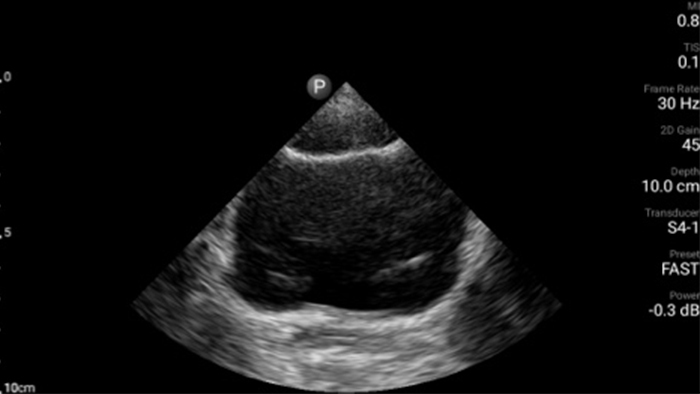

Every second counts in cardiac care

Heart attack patients need immediate care. Lumify's cardiac presets can help patients get diagnosed faster to improve their outcomes.

Lumify S4-1 broadband phased array transducer

• 4 to 1 MHz extended operating frequency range • 2D, color Doppler, M-mode, advanced XRES and multivariate harmonic imaging • High-resolution imaging for abdominal and cardiac applications: Cardiac, OB/GYN, Lung, Abdomen and FAST imaging preset optimizations Lumify aids life-saving technology in prehospital setting